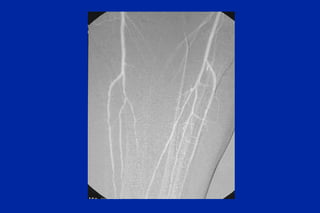

Este documento resume los principales tipos y técnicas de angiografía. Describe brevemente la angiografía, arteriografía, flebografía y linfografía, así como las técnicas de contraste y materiales utilizados. También explica los principales accesos vasculares, la técnica de Seldinger, la angiografía por sustracción digital y algunas técnicas endovasculares comunes.